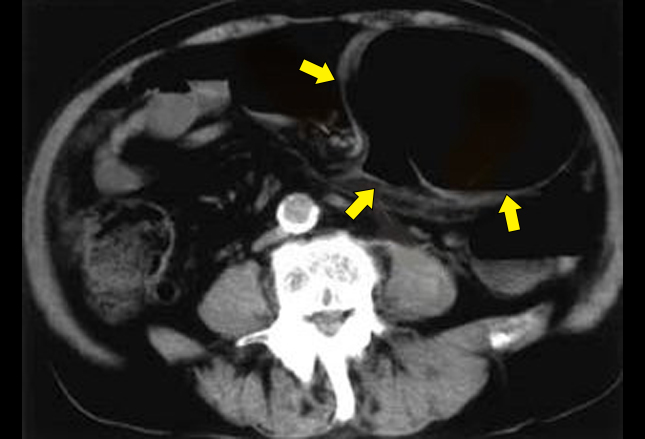

通过CT检查

,可以看见近端结肠正常表现,乙状结肠扩张(如下图箭头所示)。长期卧床患者和精神障碍患者的风险最大,因为精神药物可以减缓肠道蠕动。冗余乙状结肠(乙状结肠延伸,导致一个冗余环路)也是风险因素。患者一般表现为急性腹痛

、痉挛、腹胀和便秘。

通过静脉(IV)输液和广谱抗生素使用,患者病情初步稳定。对病情不稳定的患者,手术是最佳疗法,但对病情稳定的患者,内镜减压可能是合适的初始方案。